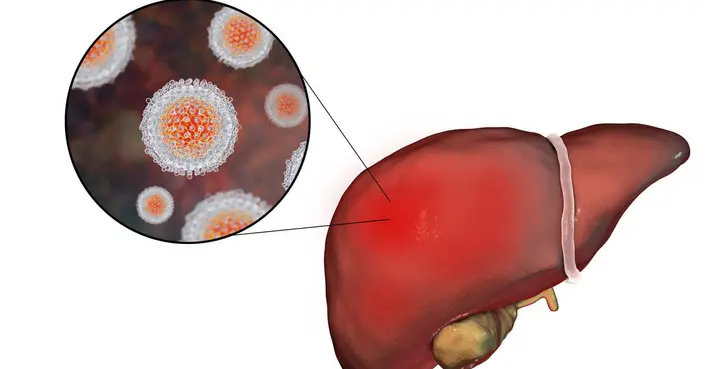

- التهاب الكبد الفيروسي: العدوى الفيروسية التي تسبب التهاب الكبد.